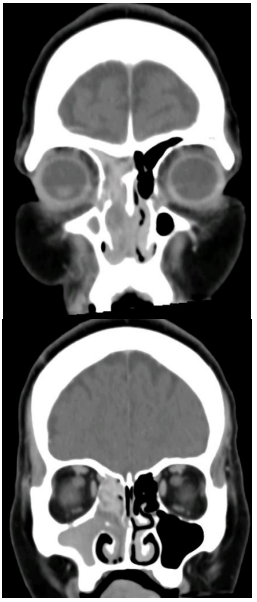

Adolescente do sexo masculino, de 16 anos de idade, com

obstrução nasal e rinorreia anterior e posterior mucopurulenta,

todos a esquerda. Apresenta endoscopia com pólipo nasal

ocupando toda a narina esquerda, sendo visível pela coana

do lado direito também. Vem com a seguinte tomografia dos

seios da face. Assinale a alternativa que apresenta o

diagnóstico mais provável.